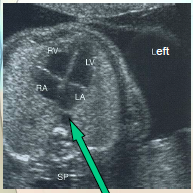

can you identify the fetal lt/rt sides?

also note the lung echotexture

what plane was this taken in?

how can you tell?

sp is spine in trans

what does the T sign mean?

why does it look that way?

it rules out 90% of pathology

both valves are closed

what part of the heart is always closest to the AO?

rt atrium

how can you tell the baby position?

what can you say abou the lungs?

what can they indicate?

by the diaphragm (A, P, S, I) long to baby

Echotexture is homogeneous with medium level echoes

Early in gestation lung echogenicity is less than or equal to liver

Later in gestation lung echogenicity is greater than liver

Lung echogenicity can be an indicator for lung maturity & can be verified by amniocentesis with L/S (Lecithin-Sphingomyelin) ratio. In this image b/c the lung echogenicity is > liver you can tell it’s further along ~ 30wks